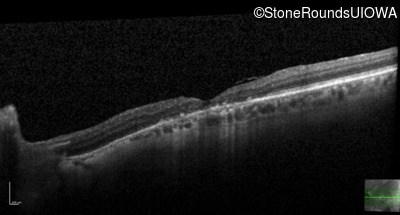

This 52 year old man had normal vision until his mid 30's when he began to have trouble distinguishing colors. the issuing 10 years he had a gradual loss of visual acuity accompanied by increasing photophobia.

| Age at visit: 55 years |

| Age at visit: 58 years |

| Age at visit: 61 years |

| Age at visit: 64 years |